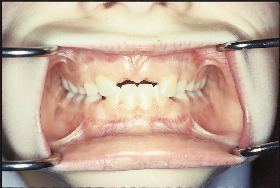

Sự hiện diện răng dư là nguyên nhân phổ biến nhất gây không mọc được răng cửa giữa hàm trên. Nó cũng có thể là nguyên nhân chậm thay răng sữa. Vấn đề thường được chú ý với việc mọc răng cửa bên hàm trên cùng với tình trạng không mọc được một hoặc cả hai răng cửa trung tâm (Hình 5 và 6). Răng dư ở các vị trí khác cũng có thể gây không mọc được các răng lân cận.

Sự chiếm chỗ

Sự hiện diện của răng dư có thể chiếm chỗ răng vĩnh viễn. Mức độ chiếm chỗ có thể từ xoay nhẹ trục răng đến chiếm chỗ hoàn toàn. Sự chiếm chỗ của răng cửa là đặc trưng phổ biến trong đa số trường hợp liên quan đến chậm mọc răng.